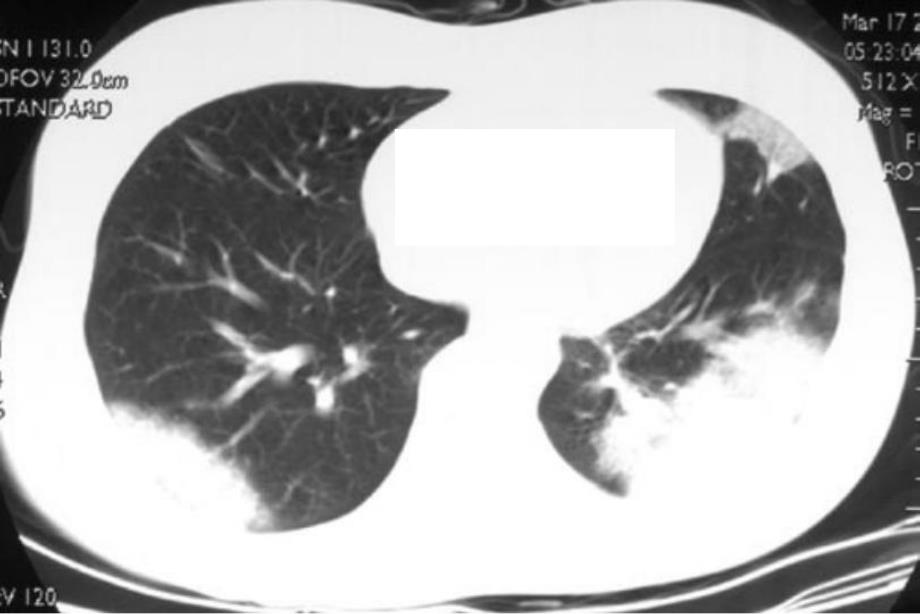

3、变 肺实质病变的不均一性肺实质病变的不均一性 通气量的大小通气量的大小 峰压切换过大峰压切换过大 平均肺泡压过高平均肺泡压过高 通气频率通气频率 通气的时间通气的时间 分泌物滞留分泌物滞留VILIVILI的诊断的诊断 警惕:认识高危因素警惕:认识高危因素 尤其在人尤其在人-机协调较差时机协调较差时 查体查体 X X-线征象线征象 标记物标记物肺保护性肺保护性 通气策略通气策略 避免潮气量过大:小潮气量通气避免潮气量过大:小潮气量通气(限压限压)避免终末气道的反复开闭:避免终末气道的反复开闭:PEEPPEEP的应用的应用CT scan at 0 cmH2O PEEP(A),and at 15 c

4、mH2O PEEP(B)of a patient with A R D S e x p d u e t o s e p s i s 容积控制通气的呼吸力学曲线容积控制通气的呼吸力学曲线气道峰压(气道峰压(PD)的影响因素)的影响因素 吸气流速吸气流速 气道阻力气道阻力 潮气量潮气量 胸肺顺应性胸肺顺应性 呼气末正压(呼气末正压(PEEP)内源性呼气末正压(内源性呼气末正压(PEEPiPEEPi)平台压(平台压(PS)的影响因素的影响因素 潮气量潮气量 胸肺顺应性胸肺顺应性 PEEPPEEP 内源性呼气末正压(内源性呼气末正压(PEEPiPEEPi)流速或气道阻力流速或气道阻力对气道对气道 峰压